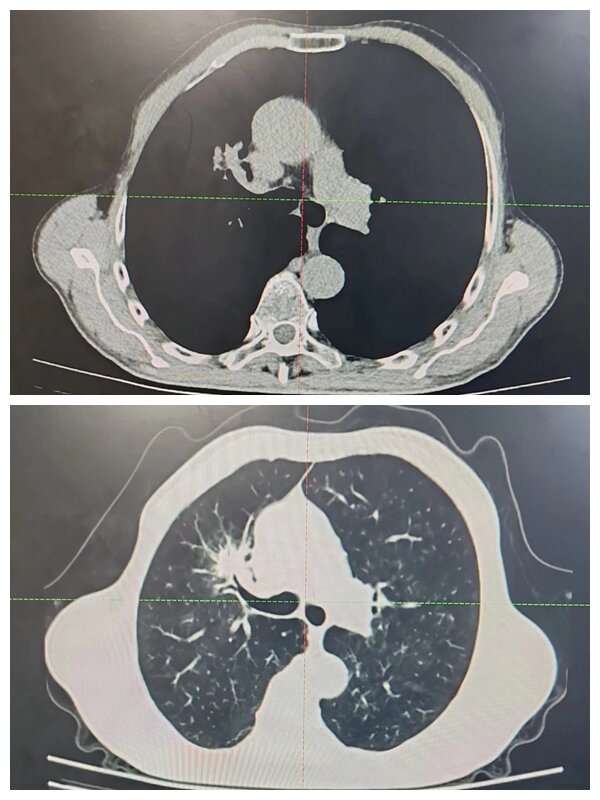

放療前

“超分割”放療治療前,需要讓患者保持一個輕松舒適的仰臥位,用熱塑膜固定,通過增強CT掃描并上傳至計劃系統(tǒng),并勾畫病灶和周圍正常器官。放療科物理師和醫(yī)生制定治療計劃并評估,之后通過三維劑量驗證設(shè)備,做劑量驗證,然后行治療前圖像引導(dǎo),從而保證了治療靶區(qū)的精準(zhǔn)性、位置的準(zhǔn)確性及劑量的準(zhǔn)確性。